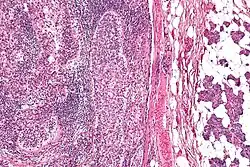

Micrograph of a sebaceous carcinoma (left of image) metastatic to the parotid gland (right of image). H&E stain. | |